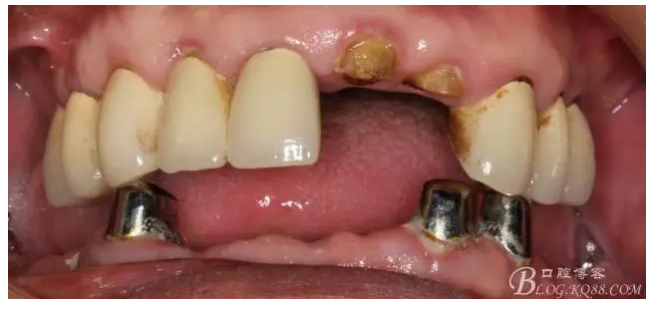

還要有足夠的牙本質(zhì)肩領(lǐng),大家現(xiàn)在可以看到患者的下頜套筒冠還是非常好的

修復(fù)后照片,

患者的口腔衛(wèi)生保持的不好,有大量的軟垢附著,

雖然牙根折斷了,但是從這張片子可以看出我們的套筒冠還是很堅(jiān)挺的,有牙齦的退縮,但是牙槽骨致密程度非常好,值得欣慰

最近復(fù)查的照片,牙周維護(hù)好一些了,畢竟是一個(gè)80歲的老爺爺了,每次來拄著拐,還要跟著很多人攙扶著過來很不容易了。